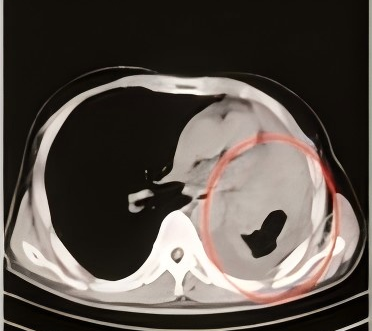

68岁患者,因长期咳嗽、气喘、气急等症状前来我院呼吸与危重症医学科就诊,在进行CT检查后,发现患者右肺存在肿瘤,进一步完善相关检查后,诊断为右肺鳞癌IIIB期,因考虑到患者肿瘤较大,需切除大部分肺组织,对肺功能影响非常大,在充分尊重患者意愿下,科室为患者制定了多种治疗方案,最终患者选择了CT引导下经皮肺穿刺碘125粒子植入治疗。综合治疗5月后,患者病灶明显缩小,2年后复查,患者病灶稳定。

碘125粒子植入术后

综合治疗5月后

综合治疗2年后